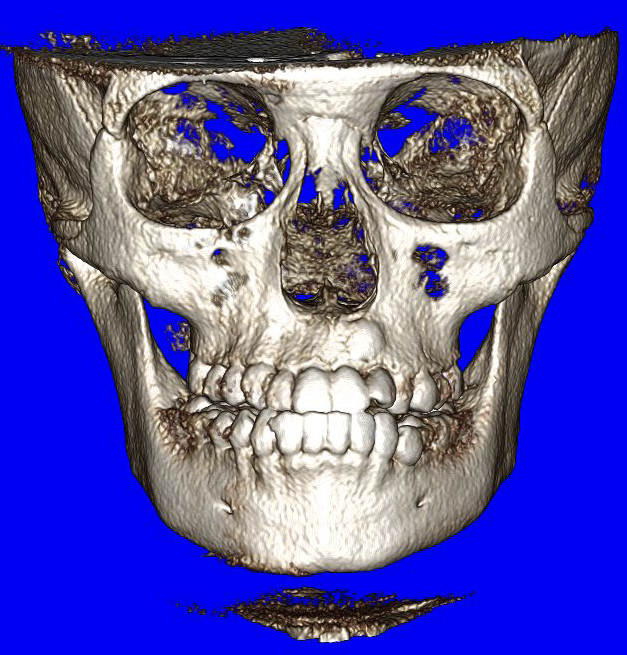

Meet Felix the iCAT! This the name of our 3D X-ray machine. At Buena Vista Orthodontics, we utilize state-of-the-art iCAT 3D imaging technology to provide comprehensive diagnostic capabilities. Nothing hides from us. In 3D, we could capture detailed images of your This advanced cone beam CT teeth, bone, TMJ, airways and much more, giving us a superior diagnostic capabilities.

Why iCAT 3D Imaging? Just look and see for yourself!

The iCAT system visualizes areas that traditional X-rays cannot show, including tooth roots, bone density, airway passages, and TMJ structures. This enhanced imaging enables us to create more accurate treatment plans and identify potential complications early.

Many Views from

One Low-Radiation Xray!